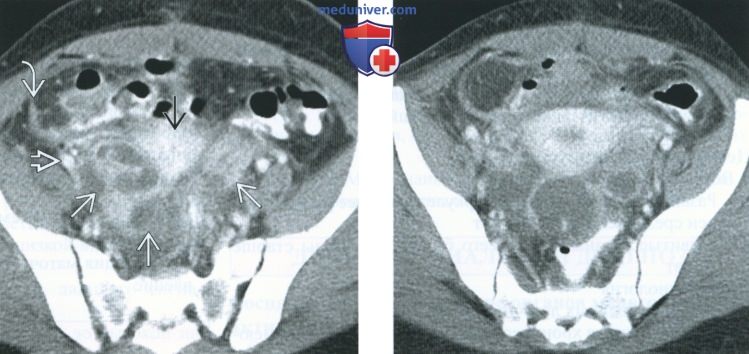

КТ диагностика тубоовариального абсцесса: Подходы и изображения

Раздел: Объективный взгляд